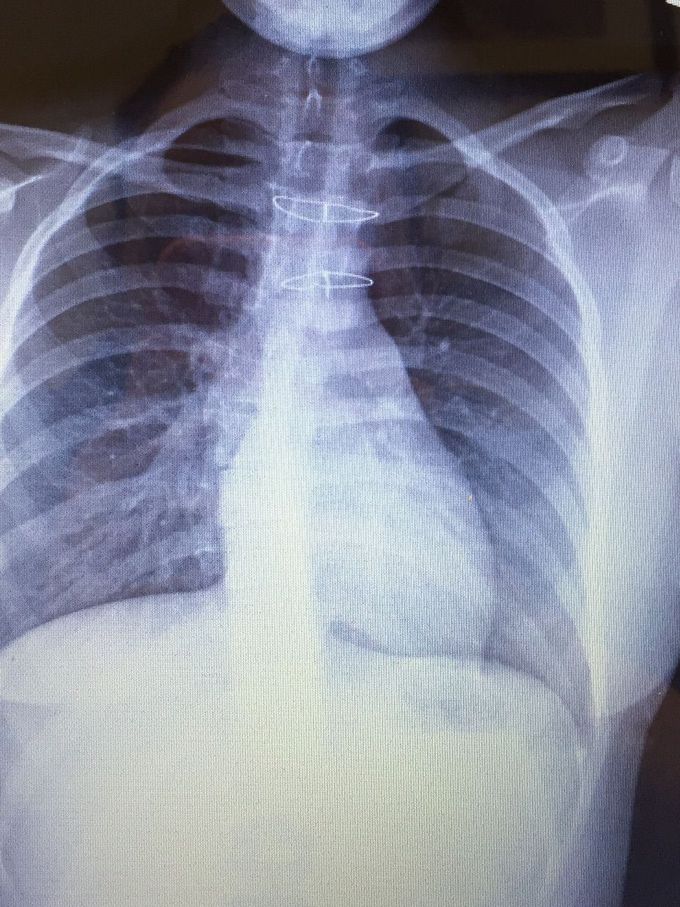

From medizzy.com

2 sternal wires placed after chest was cracked to fix aorta MEDizzy How To Fix A Broken Sternum learn how to care for a broken sternum, a long, flat bone in the centre of the chest. Find out when to call for help, what. learn how to care for a broken sternum, which can take 3 months or longer to heal. learn about the common causes, symptoms and diagnosis of a fractured sternum, a serious. How To Fix A Broken Sternum.